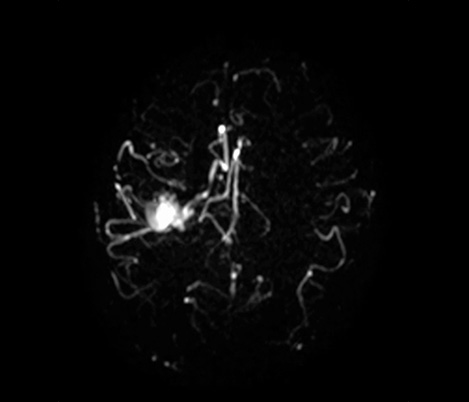

Casos clínicos de praticamente todas as anatomias Explore mais de 100 casos clínicos dos seus colegas do mundo inteiro, que demonstram como a tecnologia de RM digital da Philips fortalece os seus recursos de diagnóstico por imagem.